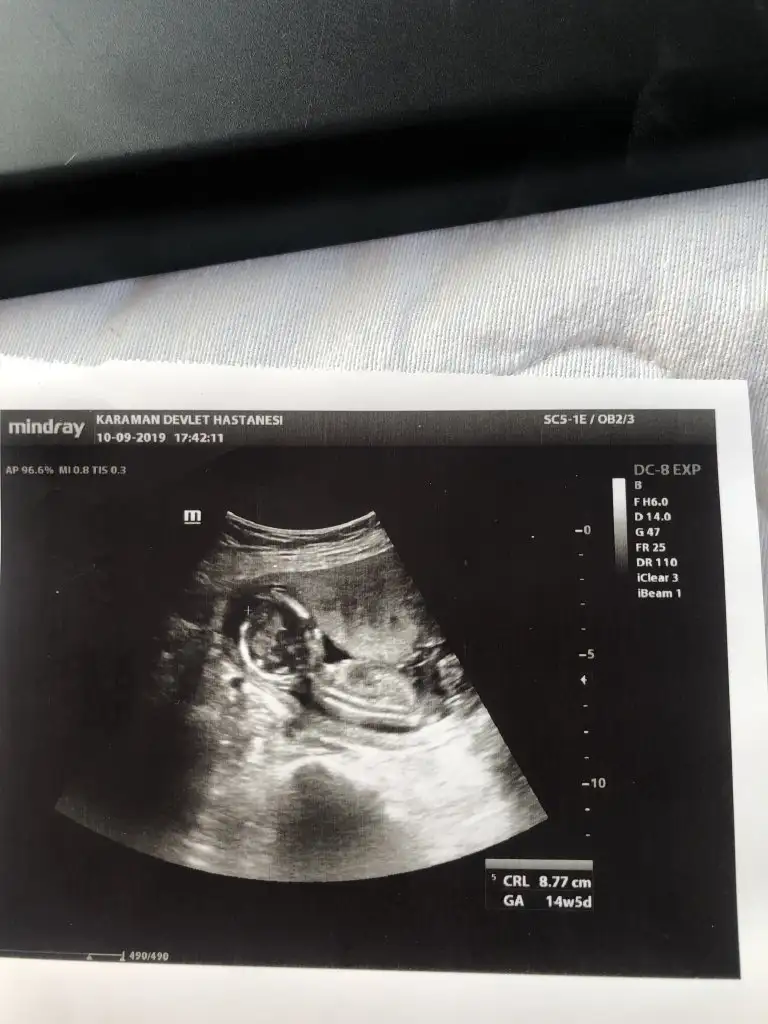

14+ 5 de nub olmaz 11 yada 12 haftanda nub kızdı tahminimArkadaşlar merhaba 14 haftalık ultrasona yorum yaparmısınız